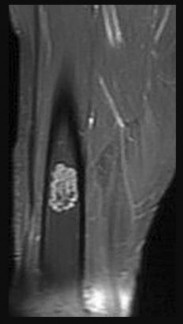

Figures 7a through 7d are the radiograph, MR images, and biopsy specimen of a 35-year-old man who has a painful, slowly enlarging knee mass. Which chromosomal translocation is characteristic of this pathology?

Synovial sarcoma is a soft-tissue sarcoma that usually occurs in young adults. Synovial sarcoma often causes pain, unlike most soft-tissue sarcomas, which generally do not cause pain. Imaging characteristics include soft-tissue calcifications on plain radiographs and a heterogeneous mass that is generally isointense to muscle on T1-weighted images and hyperintense to muscle on T2-weighted images. There are biphasic and monophasic types of synovial sarcoma. The biphasic

type, which is depicted here, has both spindle cell and epithelial components and will stain for both vimentin and cytokeratin. More than 90% of patients with synovial sarcoma have a characteristic genetic translocation of t(X;18), which results in the fusion protein SS18-SSX. This translocation can be stained for use of florescence in situ hybridization technology. t(11;12) is seen in Ewing sarcoma. T(9;22) is seen in extraskeletal myxoid chondrosarcoma. t(12;16) is seen in myxoid liposarcoma.